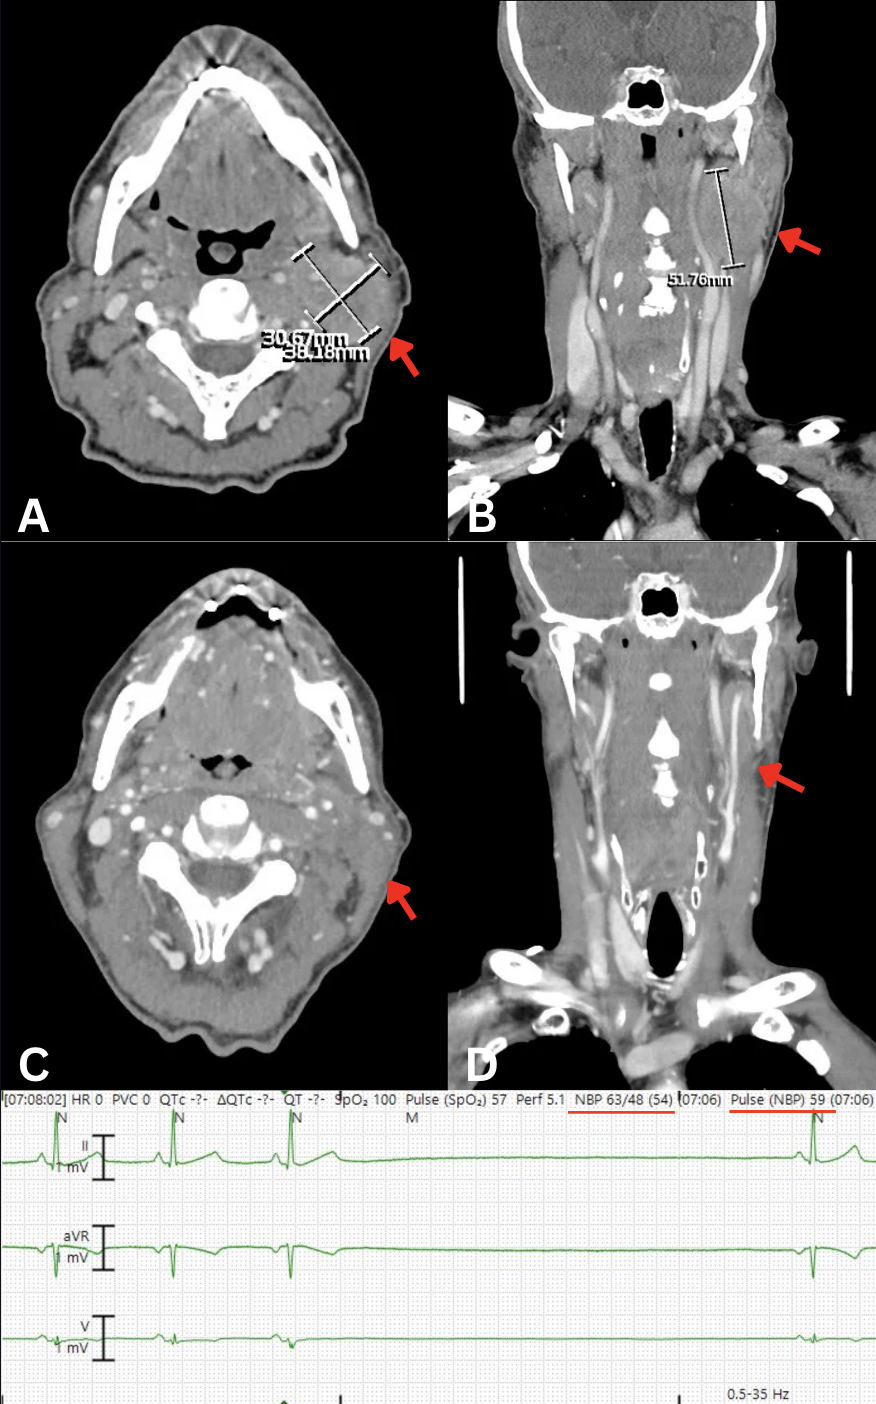

A 66 year old man with untreated L tonsillar SCC presented with recurrent syncope, hypotension, sinus bradycardia and sinus arrest up to 6 seconds as observed on telemetry (figure 1, bottom). Symptoms were atropine responsive and reliably reproduced with head turning to the L or palpation. CT neck (figure 1A-B) showed extension of the tumor into the L carotid body and adjacent vagal sheath. Echocardiogram revealed no structural heart disease. Pacemaker implantation was deferred due to suspected reversible vasovagal mechanism. He received a course of steroids, targeted cancer therapy with weekly Cetuximab infusion and daily radiation to the neck mass. After treatment initiation, the patient remained hospitalized for 3 days with no recurrent syncope or bradycardia observed. He continued outpatient treatments with resolution of his neck mass (figure 1C-D) and had no syncopal episodes over the next year.